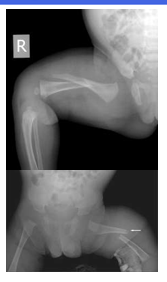

• Fractures

•Mid-shaft fractures of the humerus are more common in abuse than in  non-abuse, whereas supracondylar fractures are more likely to have non-  abusive causes

• Bucket handle fractures

Metaphyseal fractures

Corner fractures